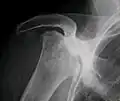

Avascular necrosis most commonly affects the ends of long bones such as the femur (the bone extending from the knee joint to the hip joint). Other common sites include the humerus (the bone of the upper arm),[7][8] knees,[7] shoulders,[8] ankles and the jaw.[7]